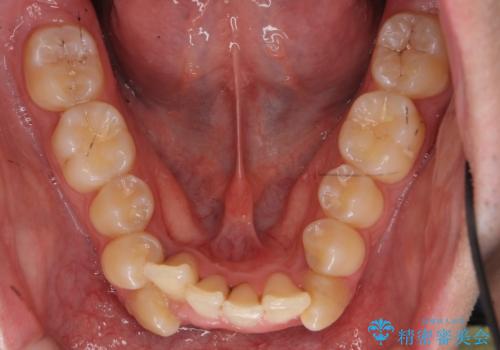

前歯のがたつき 下の八重歯

- 前歯のがたつきを主訴に来院。

上下左右の小臼歯を抜歯しています。

下のがたつきが大きいため、抜いたスペースをしっかり利用して並べるため矯正用インプラントを使用しています。